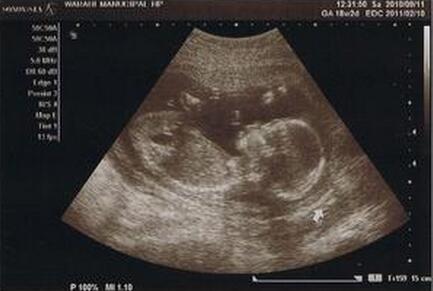

刚开始怀孕的妈咪总是对宝宝充满幻想,孕18周胎儿是什么样的呢?宝妈又该注意哪些事项呢?

一、孕18周胎儿发育情况

你的宝宝现在从头到臀部大约长13~15厘米,重160~198克。骨骼几乎全部是类似橡胶似的软骨,以后会变得越来越硬。薄薄的皮肤下的血管清晰可见,胸脯不时地鼓起来、陷下去,这是胎儿呼吸的表现,胎儿口腔里流动的是羊水而不是空气。

怀孕18周时的胎儿在忙着伸胳膊和蹬腿呢,也就是胎动,这周胎儿的活动越来越频繁。一般18-20周就可以感觉到胎动,刚开始的胎动就像顶小水泡一样的。孕妈妈要仔细去感受哦~

2.孕16—18周你将进行第二次产检,首先你必须做基本的例行检查,包括:称体重、量血压、问诊及看宝宝的胎心音等。孕18周羊水正常值应是在3—7CM之间。平时多喝一些汤水、豆浆,有助于提升羊水质量。